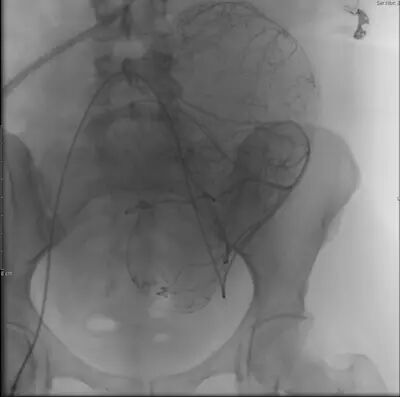

图 2 为子宫肌瘤栓塞术中